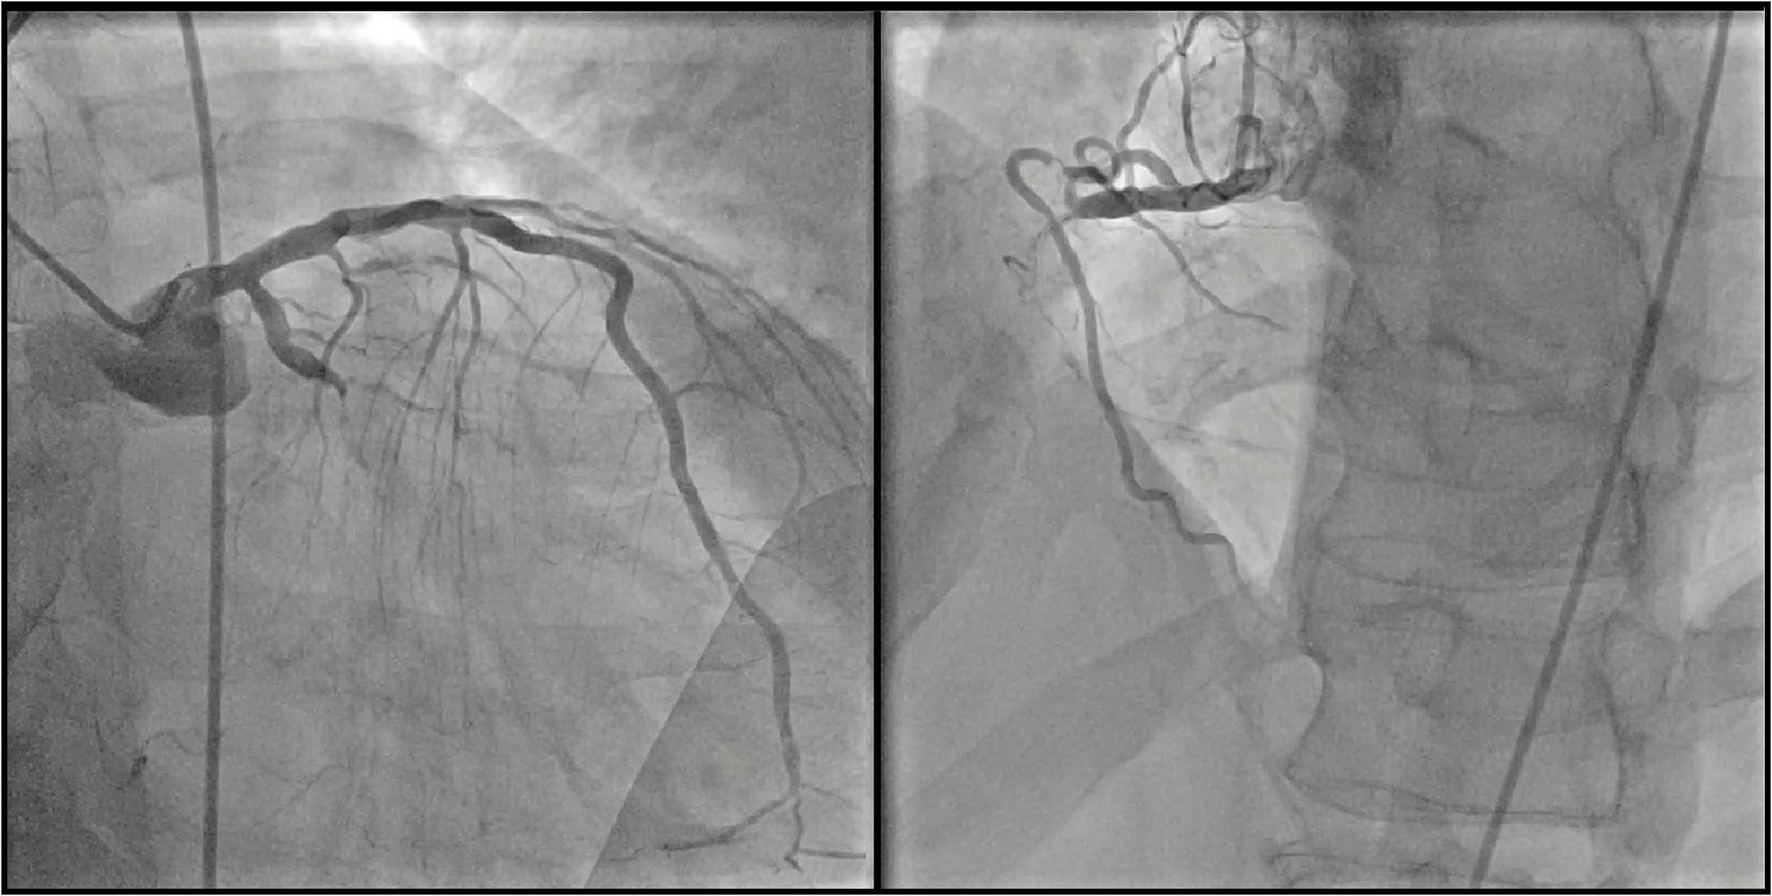

Figure 1

Coronary angiography. Left panel: chronic total occlusion of the mid left circumflex coronary artery. Right panel: chronic total occlusion of the proximal right coronary artery.